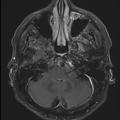

Pachyméningite sous-tentorielle

MENINGITE